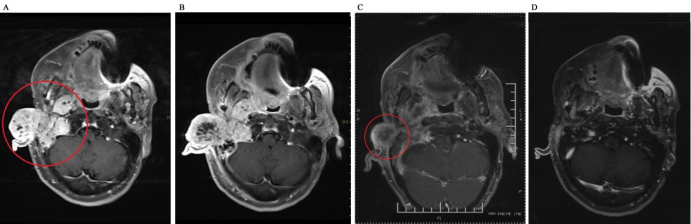

5例患者均完成了碳离子治疗,目前平均随访期15.8个月(13.0-20.0个月),随访至12个月时,1例达到CR,3例达到PR,1例上颌窦ACC患者治疗前已有双侧颈部II区淋巴结转移,在治疗后6月出现肺部转移疾病进展,疗效评价为PD,目前存活。分析疾病进展原因为碳离子治疗前已出现颈部淋巴结转移,建议碳离子治疗结束后规律进行全身静脉化疗,但患者并未按时执行。12个月OS为100%,LC为100%,PFS为80%。图1显示了1例诊断为腮腺腺样囊性癌碳离子治疗剂量分布图;图2为碳离子治疗前、治疗后及治疗后5月影像学资料疗效对比,治疗后5月疗效达CR;图3为体表肿瘤大小变化对比。

图3 碳离子治疗前后CT图像 A. 治疗前;B. 治疗后SD; C.治疗后1月PR;D.治疗后5月CR

Figure 2 CT images before and after CIRT A. Before treatment; B. SD after treatment; C. PR after 1 month after treatment D. CR after 5 months after treatment

注:PR.部分缓解;CR.完全缓解;

图3 碳离子治疗前后肿瘤大小变化图 A.治疗前;B.治疗10次;C.治疗后1月PR;D.治疗后5月CR

Fig.3 Images of tumor size change before and after carbon ion radiotherapy A. before treatment B. 10 fraction after treatment C. PR after 1 month after treatment D. CR after 5 months after treatment